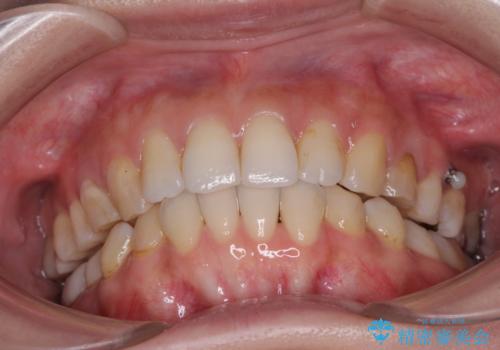

- 失活により変色した歯と不揃いな口元を気にして来院された患者様です。

口元をインビザラインにより歯列を整え、その後に失活している奥歯をオールセラミッククラウンにて補綴治療することとしました。

長時間のマウスピース装着と、患者様自身でのゴムかけに協力いただき、自然な口元に仕上げることができました。

気になっていた変色した歯もオールセラミッククラウンで本物の歯のようになり、患者様には大変満足していただきました。